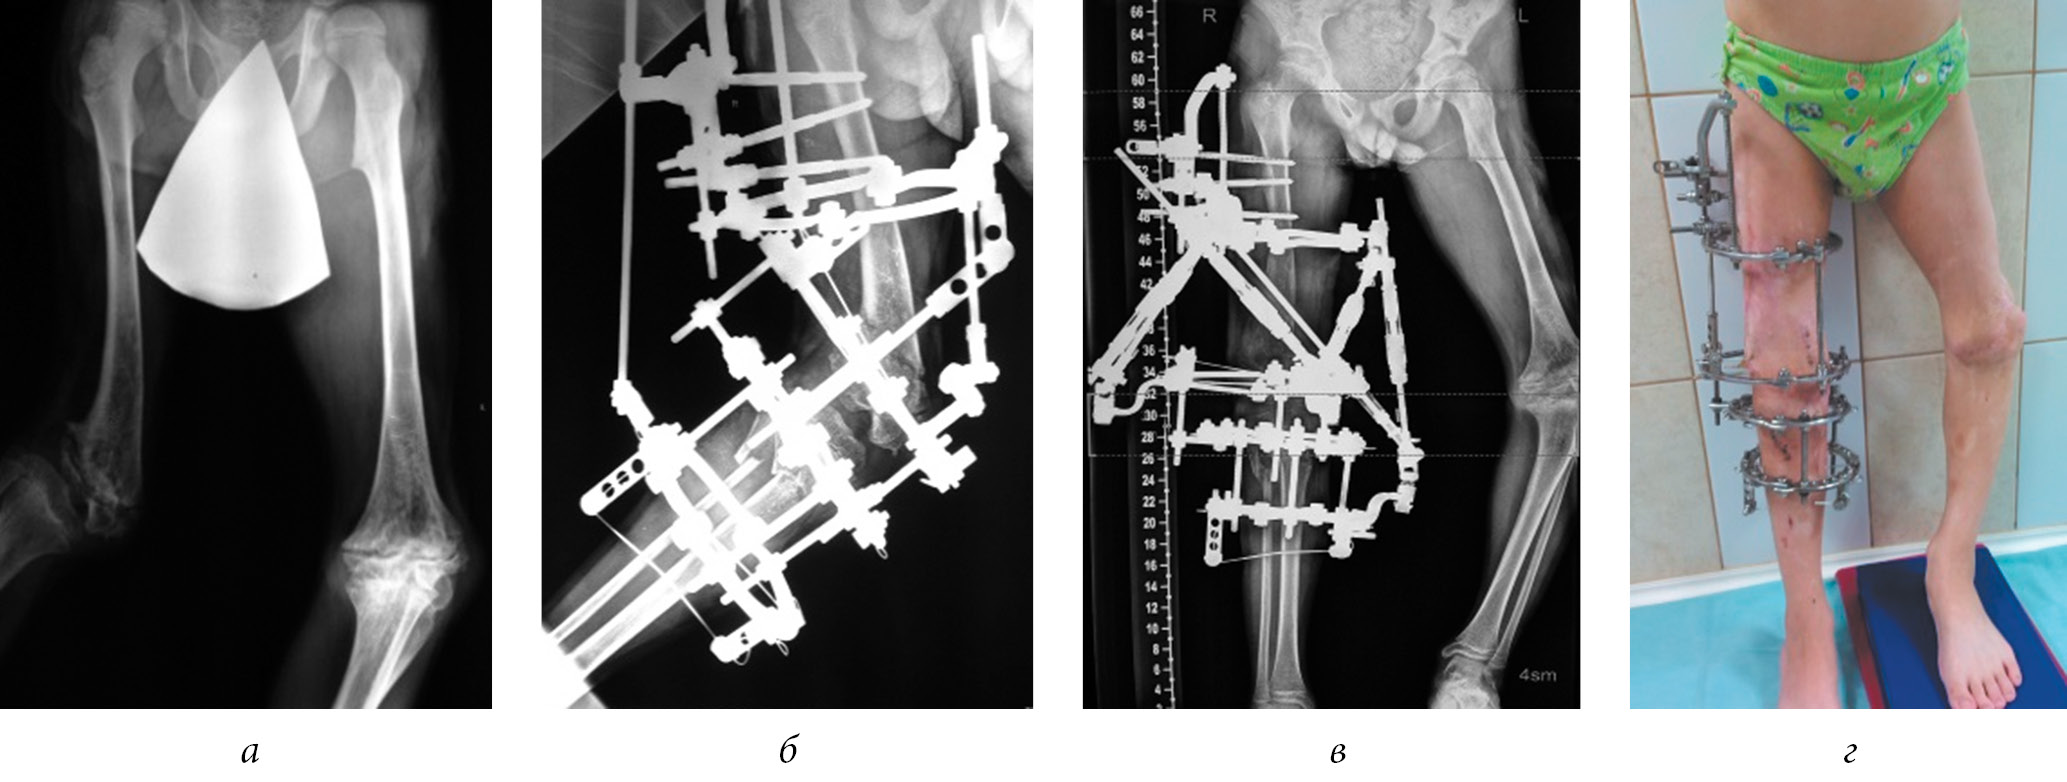

In our series of cases, in 8 out of 12 (66.7%) patients, we noted lesion to the proximal growth zones of the femoral bone with the formation of varus deformities of the necks, which necessitated surgical correction (Fig. 4).

Fig. 4. Radiographs of the hip joints of patients K. (a) and A. (b) with varus deformities of the femoral necks